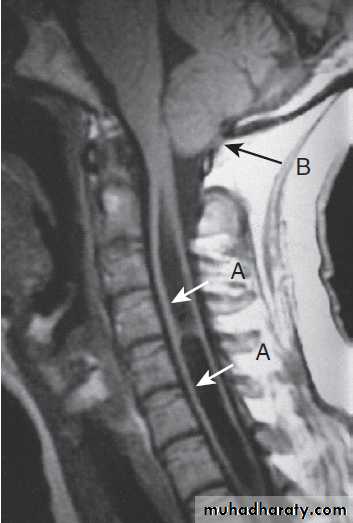

Cervical, thoracic and lumbar spine

Plain X-rays are useful in the investigation of trauma toVertebrae. MRI has transformed the investigation of these areas, since it can give information not only about the vertebrae and intervertebral discs, but also about their effects on the spinal cord and nerve roots.

Different techniques of imaging the cervical spine. A Lateral X-ray showing bilateral C6/7 facet dislocation. B Myelogram showing

widening of cervical cord due to astrocytoma (arrows). C MRI showing posterior epidural compression from adenocarcinomatous metastasis to the posterior arch of T1 (arrows).